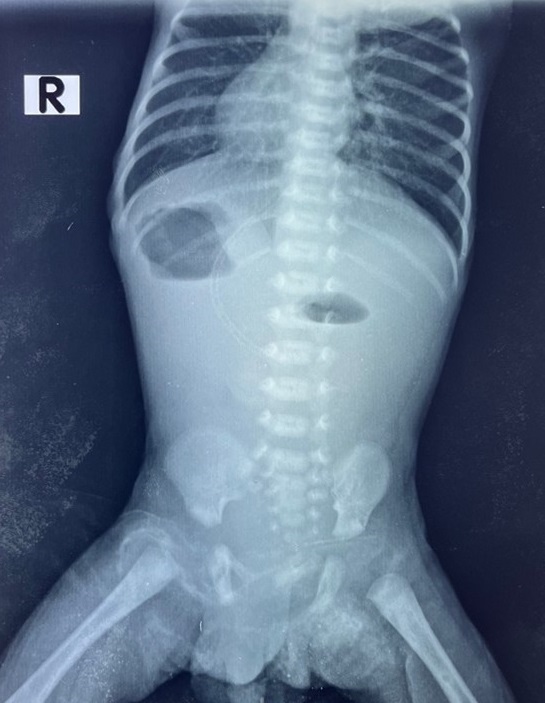

On physical examination, the baby was in good clinical condition with a soft and non-distended abdomen. Rectal stimulation revealed no meconium in it. X-ray of the chest and abdomen noted the tip of the heart on the right side, a distended stomach with an air pocket on the right side, and an absence of gas shadows in the rest of the abdomen (Fig. 1). A transthoracic cardiac Doppler ultrasound was performed and noted dextrocardia and a 7.43 mm inter-atrial communication with a left-to-right shunt without evidence of pulmonary hypertension. The diagnosis of probable duodenal atresia with situs inversus totalis was made.

Figure 1

Thoraco-abdominal radiography made on day 4 of life before admission.